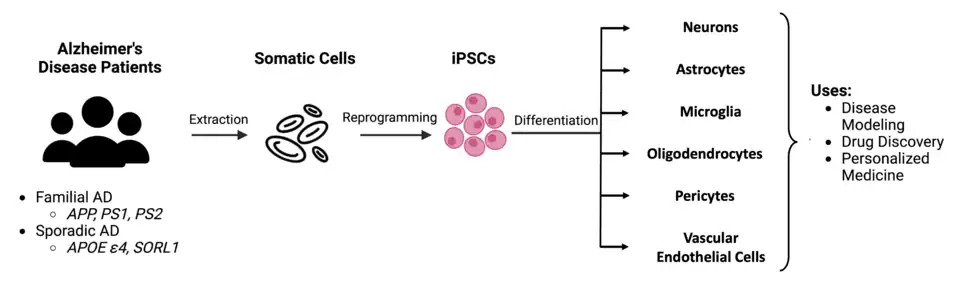

Patient-derived induced pluripotent stem cell (iPSC) lines are unique in which differentiated somatic cells are taken from Alzheimer's disease patients and reverted into pluripotent stem cells via an ectopic transcriptional "Tamanaka" factor cocktail.[11] These stem cells can then be directed to differentiate into many cell types, including neurons, astrocytes, microglia, oligodendrocytes, pericytes, and endothelial cells.[5][11] This allows these models to be generated from both early-onset familial Alzheimer's disease (FAD) patients with mutations in APP, PSEN1, or PSEN2 genes as well as late-onset/sporadic Alzheimer's disease (SAD) patients, a population which is not wholly replicated in animal models. As SAD is the most commonly diagnosed form of AD, this highlights iPSCs as key tools for understanding this form of the disease.[5] These cells can also be purchased commercially.[15][16] CRISPR-Cas9 technology can be used alongside iPSC cells to generate neurons carrying multiple FAD mutations.[5][10] One major downfall of these models are that they can inadequately resemble mature neurons as well as being more expensive and difficult to maintain.[11] iPSCs have also been shown to exhibit genomic instability and develop additional mutations when passaged (harvested and reseeded into daughter cultures) numerous times, posing both safety concerns for patient use as well as potential reproducibility problems in experimental studies.[5] Due to the nature of reprogramming procedures, iPSC cells lose cellular and epigenetic signatures acquired by aging and environmental factors, limiting iPSCs ability to recapitulate diseases associated with aging, like Alzheimer's disease. While these cultures have some limitations, many fundamental discoveries about Alzheimer's disease biology have been elucidated using this model system.